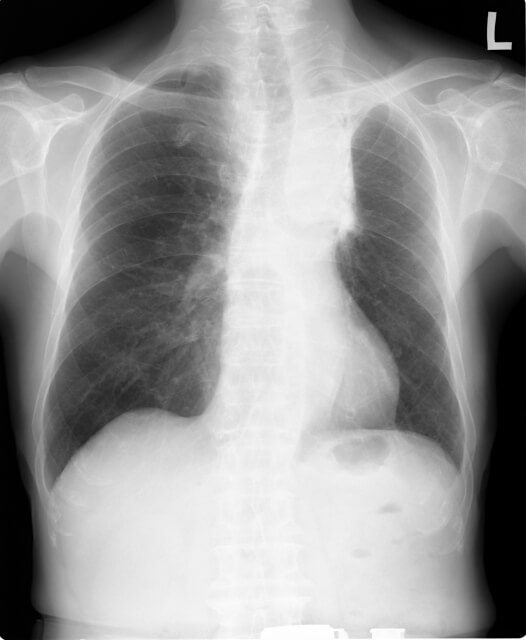

仰向けになると咳が止まらないのは、初期の肺がんの症状だった。ワクチンの副作用で小児麻痺になった子供、足が動けるようになり顔色もよくなった例。

こんにちは、李哲です。 ニハイシャ先生の治療日記、故事篇專講案例給大家聽(漢唐中醫倪海廈撰寫)(2005ー5-8発表)を翻訳しました。治らない咳と肺がんの関連性、そしてワクチンの後遺障害である小児麻痺が漢方薬で改善された内容が書かれています。参考に... -

「健康な人でも死ぬ抗がん剤を、がん患者が飲んで生き残れるはずがない」倪海厦先生が肺がん患者に伝えた衝撃の言葉

「健康な人でも死ぬ薬を、免疫力が落ちたあなたが飲んで生き残れるはずがない」 61歳の肺がん患者(肝臓・骨転移)に、主治医は「もう助からない。でも抗がん剤をすれば少し長く生きられる」と告げました。しかし、アメリカの著名な中医師・倪海厦先生は違... -